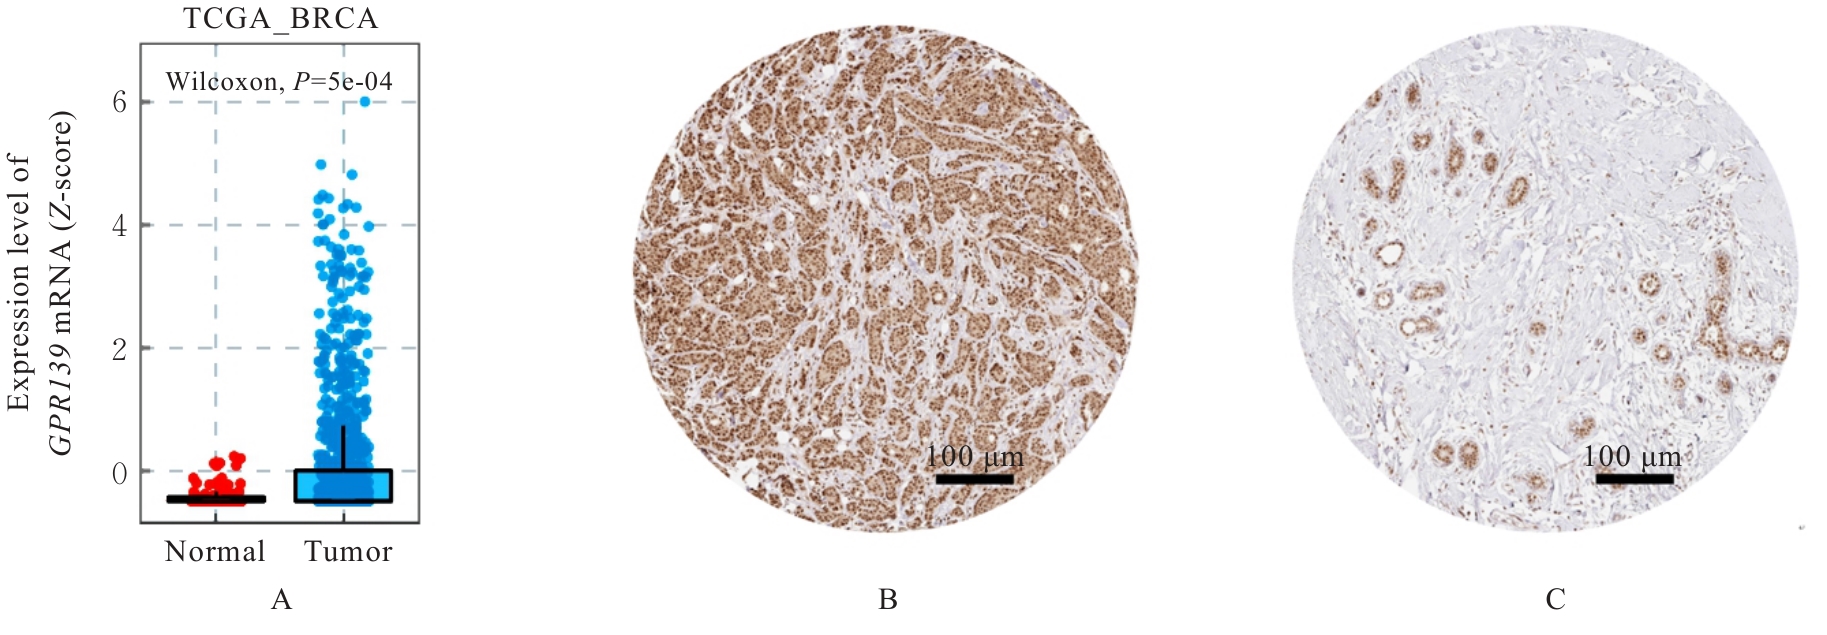

Objective To discuss the effect of silencing G protein-coupled receptor 139 (GPR139) gene on the proliferation, apoptosis and autophagy of breast cancer cells, and to clarify its possible mechanism. Methods The expression of GPR139 mRNA and protein in breast cancer tissue and normal tissue was downloaded from The Cancer Genome Atlas (TCGA) and Human Protein Atlas (HPA) databases; the GPR139 short hairpin RNA (shRNA) was transfected into the human breast cancer MCF-7 and MDA-MB-231 cell lines by lentiviral interference technology, and the cells were divided into sh-NC group (infected with negative control lentivirus), sh-GPR139 group (infected with GPR139 shRNA interference lentivirus), and sh-NC+F05 group (after infected with negative control lentivirus, GPR139 antagonist NCRW0005-F05 was added); methylthiazolyldiphenyl-tetrazolium bromide(MTT) method was used to detect the proliferation activities of the cells in various groups; Western blotting and real-time fluorescence quantitative PCR (RT-qPCR) methods were used to detect the expression levels of proliferation markers Ki-67Cyclin D1Cyclin E1, and P21 mRNA and proteins in the cells in various groups; flow cytometry was used to detect the apoptotic rates of the breast cancer cells in various groups; Western blotting method was used to detect the expression levels of adenosine monophosphate-activated protein kinase (AMPK), phosphorylated AMPK, Unc-51 like autophagy activating kinase 1 (ULK1), phosphorylated ULK1, microtubule-associated protein 1 light chain 3A/B (LC3A/B), and P62 proteins in the cells in various groups; immunofluorescence method was used to detected the expression level of LC3A/B protein in the breast cancer cells in various groups. Results The TCGA and HPA database results showed that the expression level of GPR139 mRNA in human breast cancer tissue was significantly higher than that in normal tissue (P<0.001), and the expression level of GPR139 protein was significantly higher than that in normal tissue. The MTT assay results showed that compared with sh-NC group, the proliferation activities of the breast cancer cells in sh-GPR139 group and sh-NC+F05 group were significantly decreased (P<0.01). The Western blotting results showed that compared with sh-NC group, the expression levels of GPR139, Ki67, Cyclin D1 and Cyclin E1 proteins in the breast cancer cells in sh-GPR139 group and sh-NC+F05 group were decreased (P<0.05 or P<0.01), and the expression level of P21 protein was increased (P<0.01). The RT-qPCR results showed that compared with sh-NC group, the expression levels of GPR139Ki67Cyclin D1 and Cyclin E1 mRNA in the breast cancer cells in sh-GPR139 group and sh-NC+F05 group were decreased (P<0.05 or P<0.01), and the expression level of P21 mRNA was increased (P<0.01). The flow cytometry results showed that compared with sh-NC group, the apoptotic rates of the breast cancer cells in sh-GPR139 group and sh-NC+F05 group were significantly increased (P<0.01). The immunofluorescence results showed that in MCF-7 cells and MDA-MB-231 cells, compared with sh-NC group, the expression levels of LC3A/B protein in the cells in sh-GPR139 group and sh-NC+F05 group were significantly increased (P<0.01). The Western blotting results showed that compared with sh-NC group, the expression levels of LC3A/B, p-AMPK and p-ULK1 proteins in sh-GPR139 group and sh-NC+F05 group were significantly increased (P<0.01), and the expression level of P62 protein was significantly decreased (P<0.05 or P<0.01). Conclusion Silencing GPR139 gene can induce autophagy and apoptosis of breast cancer cells and inhibit cell proliferation, and its mechanism may be related to the increased phosphorylation levels of AMPK and ULK1 in the cells.